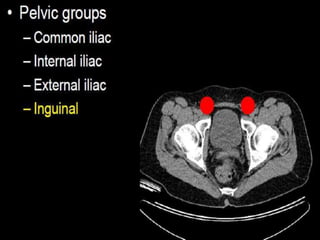

CT cross sectional anatomy.

CT – computedtomography. •Cross-sectional modality with capabilities for multiplanar reconstruction and dynamic imaging to assess vascularity •Tube rotates around the body and a circle of stationary detectors detects the penetrating x-rays forming an image.